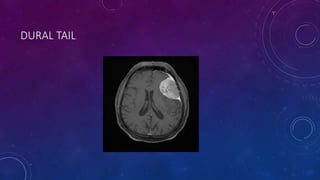

• A widely discussed feature of meningiomas is the dural tail, which represents

contrast enhancement extending along the dural margins. The histologic

composition of such dural tails is not entirely clear, with evidence supporting

either meningioma involvement or reactive dural thickening.

DURAL TAIL

(A) A THIN RIM OF LOW ATTENUATION REPRESENTS CEREBROSPINAL FLUID (CSF) TRAPPED AROUND A LARGE LEFT

FRONTAL MENINGIOMA. THIS IS A FEATURE INDICATING THE EXTRAAXIAL NATURE OF THE TUMOR. NOTE THE VASOGENIC

EDEMA IN ADJACENT BRAIN PARENCHYMA (LOW DENSITY) OUTSIDE THE CSF CLEFT (ARROWS).